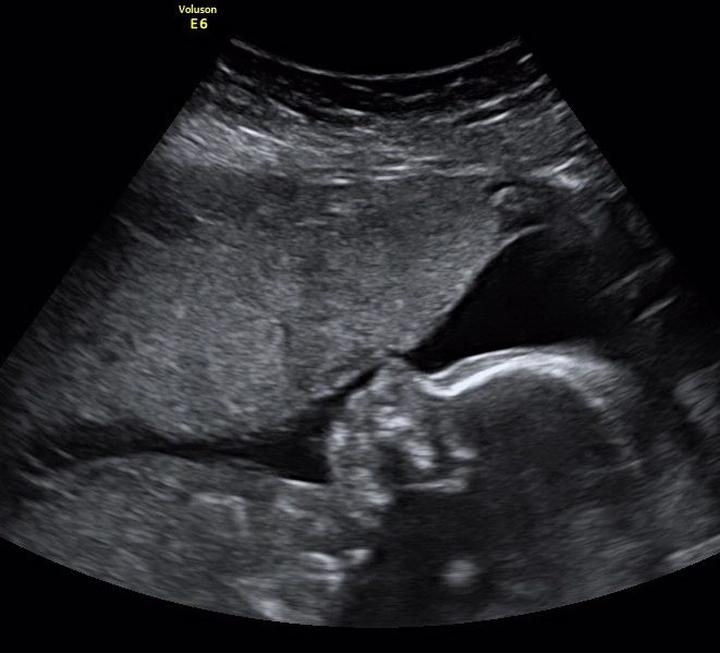

W trakcie badania lekarz stara się zmierzyć różne parametry, które stanowią cenne wskazówki dla przyszłych rodziców. Na przykład, CRL (długość ciemieniowo-siedzeniowa) to jeden z podstawowych wymiarów zarodka. Im większą wiedzę zdobędziesz, tym mniejsze prawdopodobieństwo, że później doświadczysz zaskoczenia jako „przerażony rodzic” z wynikiem USG w dłoni, na którym widnieją tajemnicze znaczki.

Interpretacja wyników USG w ciąży to zadanie, które często wprawia w zakłopotanie przyszłe mamy. Kto z nas nie doświadczał uczucia dezorientacji w obliczu mieszanki skrótów, cyfr oraz specjalistycznych terminów, które lekarze przekazują podczas wizyt? „Mówiłeś coś o NT, a może CRL? Co to w ogóle oznacza?” – pewnie niejedna kobieta, rozmawiając z innymi przyszłymi rodzicami, tak się zastanawiała. Na szczęście nie musisz być lekarzem, aby pojąć, co dzieje się w twoim brzuszku! Zrozumienie tego jest proste, jeśli wiesz, gdzie szukać informacji. Kto by pomyślał, że takie cyferki mogą tak mocno wpływać na nasze emocje, prawda?

Równocześnie pamiętaj, że każdy pomiar ma swój kontekst, a różnice między ciążami są zupełnie naturalne. Lekarze często podkreślają, że każde dziecko jest inne, co oznacza, że wyniki mogą różnić się od tych, które uzyskała twoja koleżanka. Jeśli dostrzeżesz, że brzuch twojego szkraba wygląda zupełnie inaczej, nie martw się – wystarczy, że lekarz potwierdzi, że wszystko jest w porządku. Wymiana informacji pomiędzy lekarzem a pacjentką odgrywa kluczową rolę, dlatego nie wahaj się zadawać pytań, nawet tych, które wydają się „dziwne”.